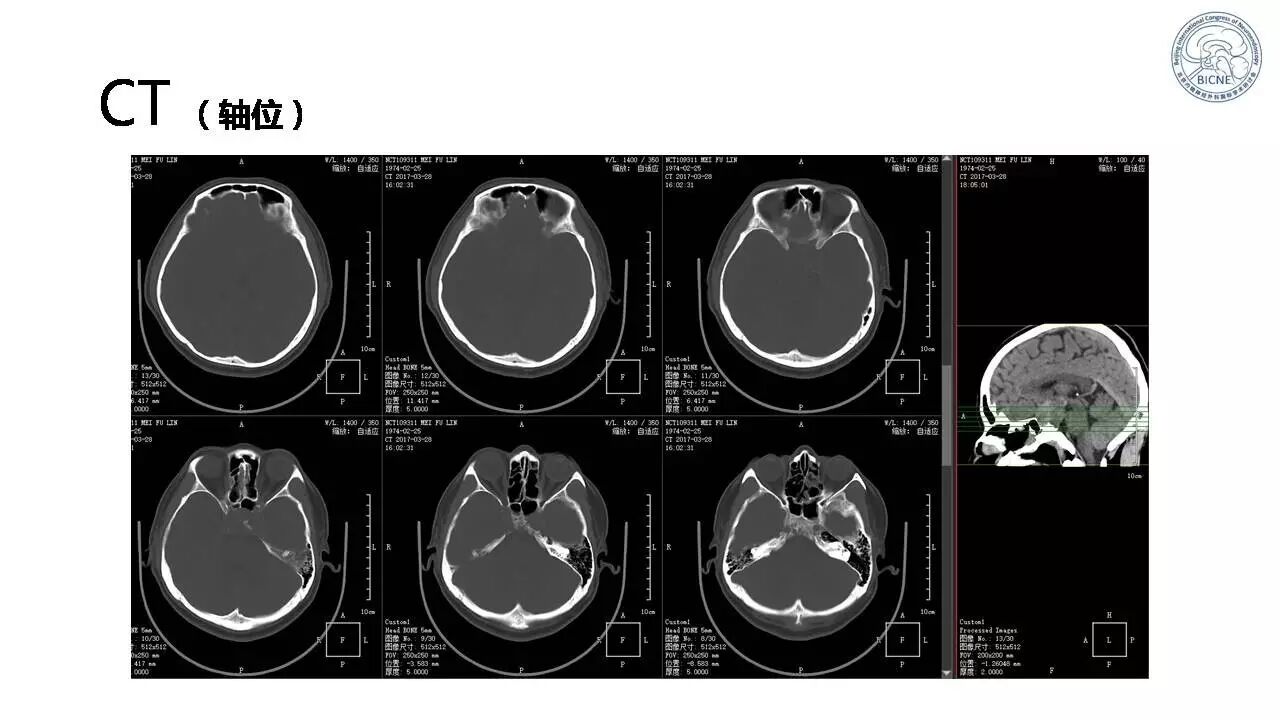

(四)张亚卓教授:复发脊索瘤经鼻内镜治疗

![]()